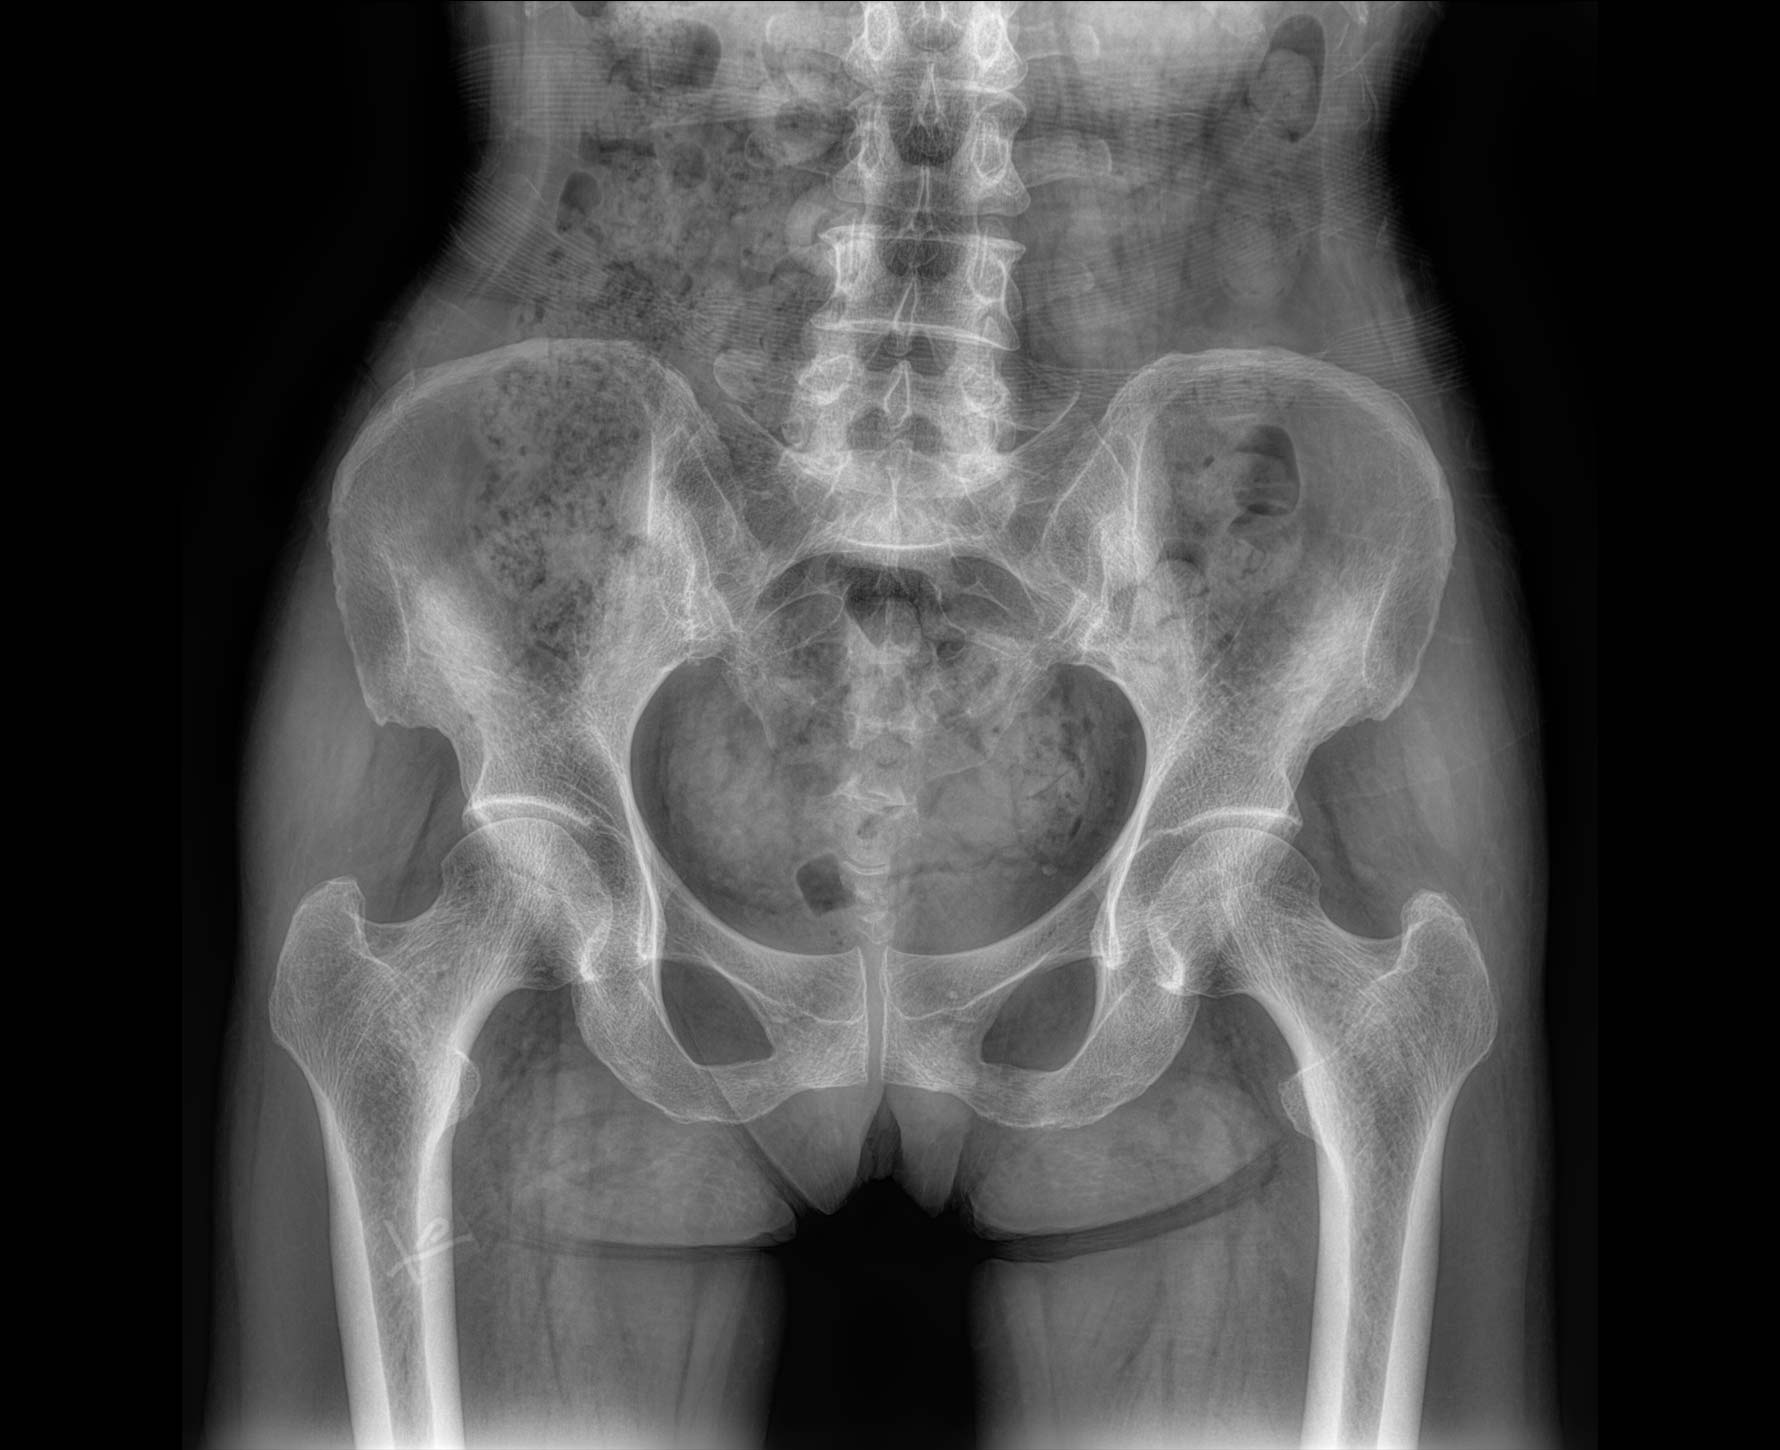

適用于全身各部位攝影

(常規攝影和特殊攝影)